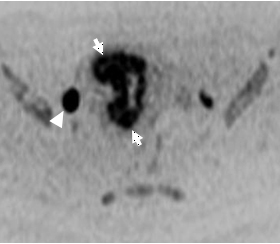

![]() 図.2 拡散強調画像 |

造影剤を使用し、撮影する事で癌の存在・広がりを正確に診断することができます(図.1矢印)。癌が子宮のどこに存在し、周囲の臓器へ浸潤しているか否かは治療方針を決定する上で非常に重要な要素となります。また、特殊な撮影法を併用することで、より癌は明瞭に描出され(図.2 矢印)、周囲のリンパ節への転移(図.2 矢頭)も確認が容易となります。